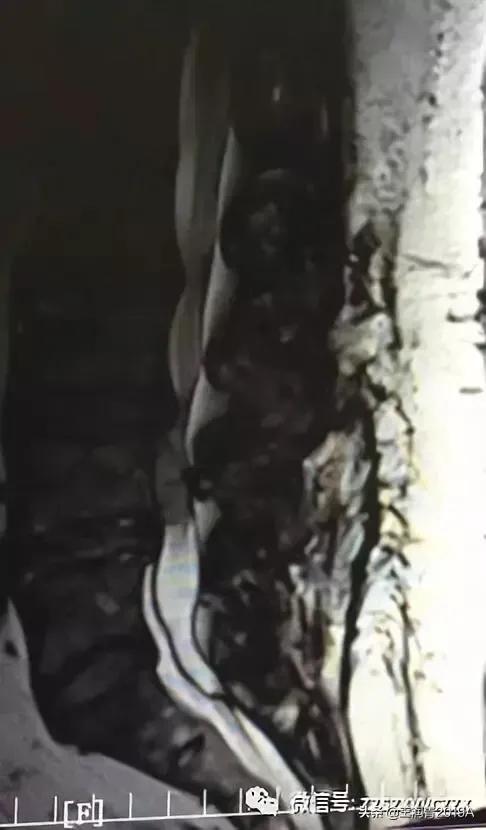

2、腰椎MR增强检查:平腰4椎体层面椎管内异常信号影,考虑腰椎间盘髓核脱出影(腰4-5)(图4-8)